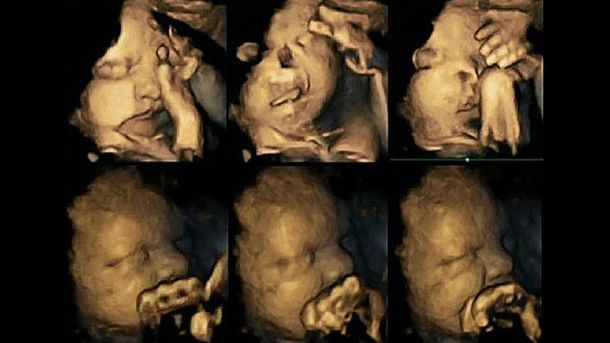

Una investigación reveló fotografías, que fueron tomadas durante ecografías en 4D, de un bebé todavía en la panza que tiene una madre fumadora. Incluso se pueden ver sus gestos de molestia.

Desde la Universidad de Durham, en Reino Unido, la doctora Nadja Reissland, del departamento de Psicología, examinó a más de 20 mujeres, según publica The Times.

De esta manera, Reissland demostró que los fetos que tienen madres que son fumadoras se tocan la boca y la cara con mucha más frecuencia que aquellos que tienen madres que no fuman.